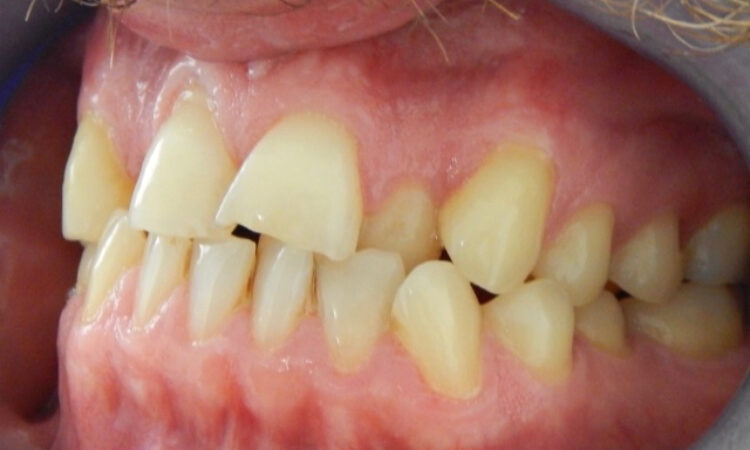

Before - puredental After - puredental

Case 20 - Invisalign®